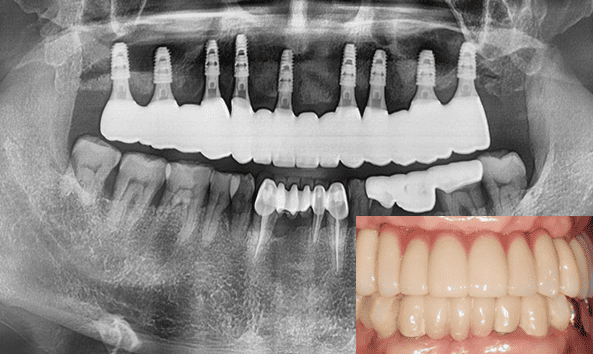

결과로 보여드리는 의료진의 노하우

- 24.12

* 임플란트 시술 시 교합이상, 신경손상, 염증 등의 부작용이 발생할 수 있습니다.

* 개인의 구강 및 치아상태에 따라 치료방법과 수가가 변동될 수 있습니다.

* 해당 사례는 의료법 제56조 2항을 준수하여 작성되었습니다.

* 본원에서 진료받은 환자이며 전후 사진의 인물이 동일인임을 밝힙니다.